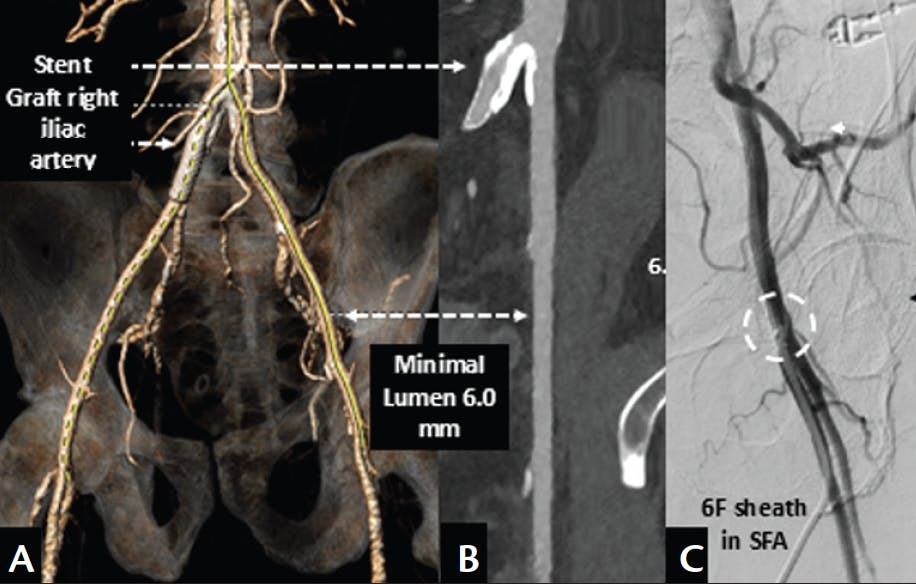

A patient in his mid 70s was admitted because of decompensated heart failure with a reduced ejection fraction and severe aortic valve stenosis. The patient’s clinical history revealed atrial fibrillation, type 2 diabetes, and chronic renal failure. Electrocardiography demonstrated a normal sinus rhythm with an incomplete left bundle branch block. Cardiac ultrasound showed an ejection fraction of 45% and severe aortic stenosis with a peak velocity of 4 m/s, an aortic valve area of 0.62 cm2, and a velocity time index ratio of 0.23. There was no aortic regurgitation. Multislice CT revealed a stent graft with mild in-stent stenosis in the right iliac artery. The left iliofemoral tract showed minimal disease but small luminal dimensions (6 mm). CT interrogation of the aortic valve demonstrated a tricuspid valve morphology with anatomic dimensions suitable for implantation of a Navitor™ bioprosthesis (Abbott).

The patient was transferred to the Erasmus Medical Center for elective TAVI under local anesthesia. Using real-time ultrasound visualization of the left iliofemoral tract, arterial access (15 F) in the common femoral artery (CFA) was achieved proximal to the bifurcation and distal to the origin of the inferior epigastric artery. A second arterial access (6 F) was achieved in the ipsilateral superficial femoral artery (SFA; 3 cm distal to the 15-F arteriotomy). Right radial access was used for cerebral embolic protection device placement in the brachiocephalic trunk and left carotid artery. Under left ventricular guidewire-driven rapid pacing, balloon aortic valvuloplasty using a 21-mm True balloon (BD Interventional) was performed. Subsequent advancement of the FlexNav™ delivery system through the small-caliber iliofemoral tract alongside the pigtail catheter went smoothly and without interruption (Figure 1). Deployment of a 27-mm Navitor™ valve was successful on the first attempt and positioned at 2- and 4-mm depth relative to the non and left coronary cusp, respectively (Figure 2). There was complete resolution of the transvalvular gradient and no residual regurgitation or new conduction abnormality. The 15-F arteriotomy was closed with an 18-F, plug-based closure device (Manta, Teleflex; Figure 1C); hemostasis at the 6-F arteriotomy site was achieved with a vascular suture device (Perclose™ ProStyle™, Abbott). The patient was discharged 4 days later without serious complications during his stay.

Figure 1. Multislice CT images of the iliofemoral tract demonstrated a stent graft in the right iliac artery (A) and minimal disease but small luminal dimensions (6 mm) in the left iliac artery (B). Digital subtraction imaging demonstrated hemostasis and vessel patency at the 15-F arteriotomy site after plug-based closure with an 18-F Manta vascular closure device (dotted circle, C).